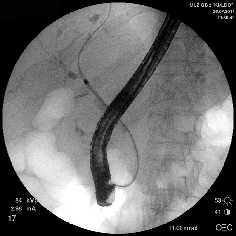

Рубцовая стриктура средней трети холедоха, холедохолитиаз

Полный блок средней трети холедоха (клипса на холедохе)

Несостоятельность культи пузырного протока

Рис. 1. Рентген-фото выявленной патологии

Rg-фото. Бужирование стриктуры холедоха

Rg-фото. Баллонная дилятация стриктуры холедоха

Rg-фото. Стентирование холедоха

Рис. 2. Наиболее часто выполняемые эндоскопические вмешательства